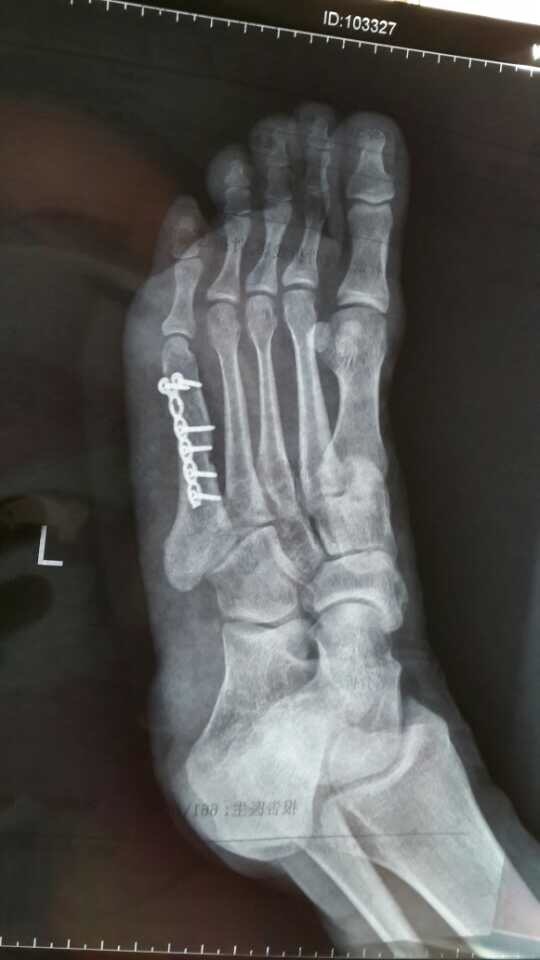

这是现在我的脚。2014年9月2日,那是一个细雨绵绵的秋日,上过3400米高山下过30米深海环过360公里青海湖的一个女子,挤公车的时候,左脚第五跖骨骨折。手术之后安了一根钢板六根钢钉,目前已有11个月,杀人越货居家旅行没有任何影响,过安检不会哔哔哔,请放心!